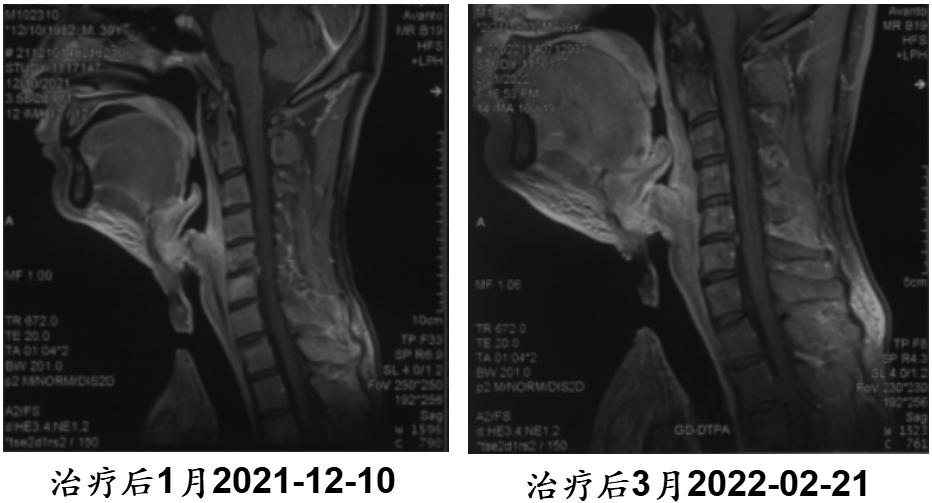

病例4:39岁下咽癌侵透颈部,合并感染脓疡

· 诊断:下咽鳞癌cT4aN2M0 IVA期,肿瘤侵透颈前皮肤,形成感染脓疡

· 难治点:肿瘤破溃+感染化脓,形成蜂窝织炎

· 重(碳)离子治疗:治疗12次

· 结果:治疗后41天,脓疡吸收,皮肤愈合;治疗后115天局部控制良好

点评:即使合并严重感染、破溃,重(碳)离子依然能“力挽狂澜”。

【病例提供医生:张一贺主任 科室:放疗中心一科】